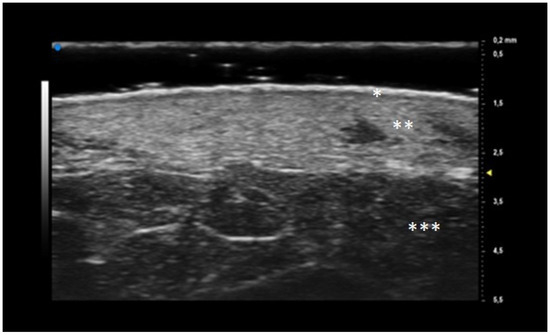

Oval hyperechoic structures were identified in the reticular and papillary dermis during the initial T0 UHFUS examination. These structures were surrounded by a consistent, homogeneous hypoechoic background. Notably, this peculiar arrangement was observed in both the pustular and ulcerative phenotypes, indicating a common underlying feature.

As the examination progressed towards the inflamed edge, these oval structures exhibited a noticeable increase in prevalence, reinforcing their association with the inflammatory process.

A statistically significant decrease in the presence of these hyperechoic oval structures was observed during the subsequent T1 UHFUS examination. This reduction in prevalence (p value < 0.05) underscores the dynamic nature of these structures and their potential correlation with the progression of the inflammatory response (Figure 2).

Additionally, a distinct finding emerged during the T0 UHFUS examination—an internal hyperechogenic structure within the oval entities. This internal structure, suggestive of a hair tract, was consistently identified during the initial examination (T0) but was notably absent in the follow-up examination (T1) (p value < 0.05) (Figure 3).

Figure 2. Pyoderma Gangrenosum (PG) Ultra-High Frequency UltraSound (UHFUS) features during the inflammatory phase (T0): oval hyperechoic structures (*) surrounded by hypoechoic borders predominantly located at the ulcer edge.

Figure 3. PG pustular lesion: hyperecoic oval structures (*), hair tract (**), hypoechoic U-shaped and V-shaped vessels (***).